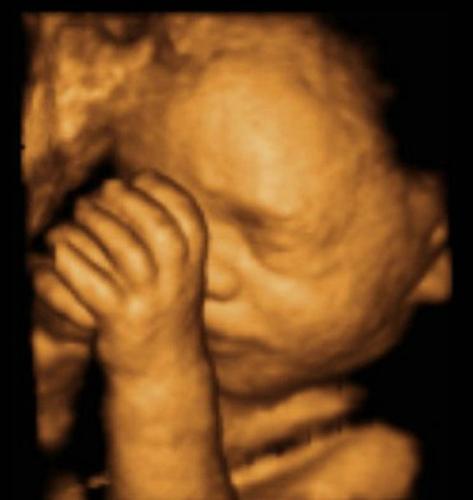

第三件事情就是吸吮手指了,别说婴儿会吸吮手指,其实胎宝宝在肚子就学会了这项技能了。胎宝宝学会了这项技能,可不是真的为了吸吮手指,而是给准妈妈分担一点事情。出生后的胎宝宝需要喝奶,就要有吸吮能力,那么胎宝宝在宫内吸吮自己的手指,就是为了出生后能够好好的喝奶!